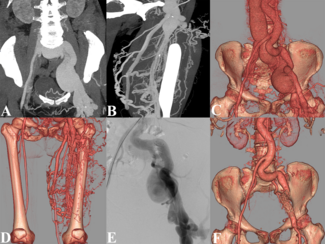

A 53-year-old woman presented with shortness of breath and fatigue for 1 week. The patient had a medical history of left thigh trauma for more than 20 years.